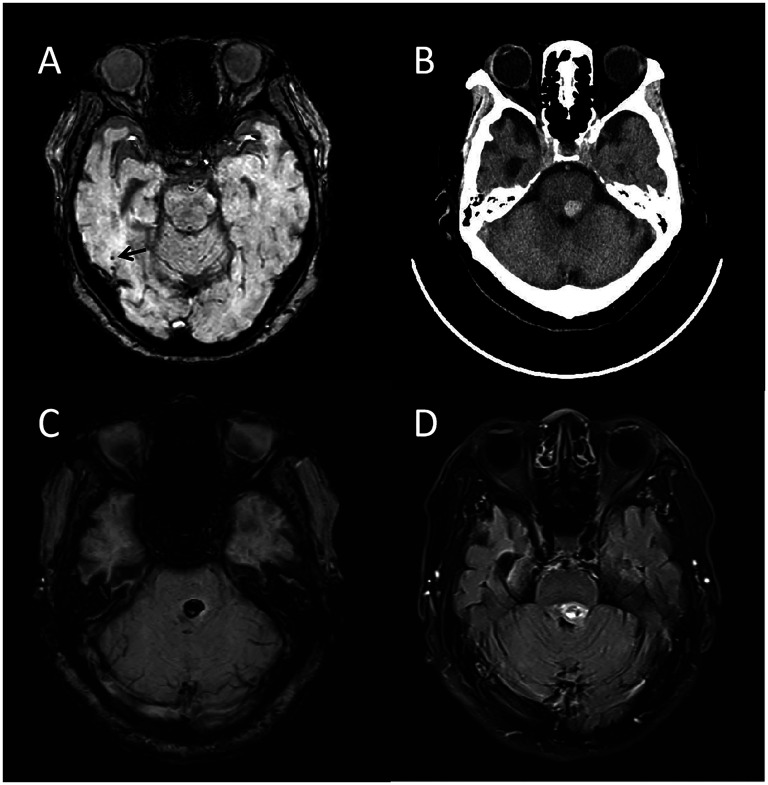

我们报告了一名76岁的轻度认知障碍患者,APOE ε3/ε3基因型患者在接受阿尔茨海默病抗淀粉样蛋白-β单克隆抗体lecanemab治疗后出现罕见的脑桥出血。她最初服用氯吡格雷和利伐沙班;利伐沙班在利卡耐单抗启动前停用。两次输注后,因心绞痛停药。随后,她接受了冠状动脉支架植入术,并接受了双重抗血小板治疗(阿司匹林和氯吡格雷)。20天后发生脑桥出血。该病例表明,即使没有APOE ε4或明显的脑血管疾病负荷,当lecanemab与强化抗血栓治疗联合使用时,出血风险也会增加。

We report a 76-year-old patient with mild cognitive impairment and APOE ε3/ε3 genotype who developed a rare pontine hemorrhage following treatment with lecanemab, an anti-amyloid-β monoclonal antibody for Alzheimer's disease. She was initially on clopidogrel and rivaroxaban; rivaroxaban was discontinued prior to lecanemab initiation. After two infusions, lecanemab was paused due to angina. She then underwent coronary stenting and was placed on dual antiplatelet therapy (aspirin and clopidogrel). Pontine hemorrhage occurred after twenty days. This case highlights heightened bleeding risk when lecanemab is combined with intensified antithrombotic therapy, even without APOE ε4 or significant cerebral small vessel disease load.